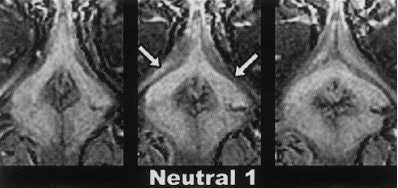

Three contiguous transverse 2-mm MR image sections, obtained in the same subject at three different times. The top images were obtained while the subject viewed neutral video material; the middle images, while the subject was aroused by erotic video material; and the bottom images, while the subject viewed the second neutral video after having been aroused by the erotic video presentation. Note the change in size of the crura of the clitoris (arrows) in response to each video segment. Figure 4, Deliganis AV, Maravilla KR, Helman JR, et al, "Female genitalia: dynamic MR imaging with use of MS-325 -- Initial experiences evaluating female sexual response." Radiology 2002; 225:791-799.

First, the group reported that a qualitative visual evaluation of the post-injection MS-325 images showed excellent enhancement of genital structures during both sessions, including increases in clitoral signal intensity and volume.

"Across all subjects, the average percent change in signal intensity from baseline to arousal increased approximately 90% in session 1 and 32% in session 2," Maravilla and colleagues reported. "For all subjects, the combined percent change of both sessions was over 108%, with a range between 16% and 260%." In premenopausal women, the average percent change in clitoral volume measured 121%; in postmenopausal women, it was 81%.